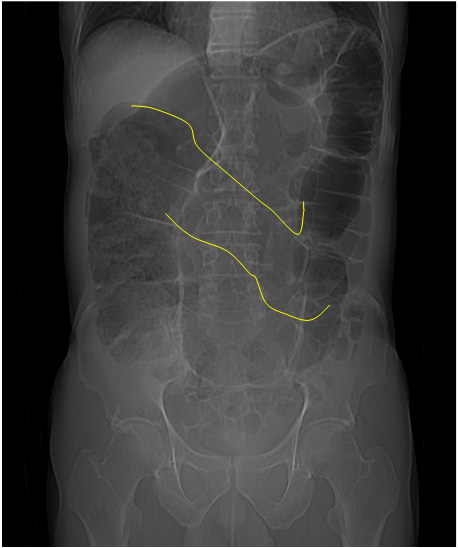

SIGNO DEL PASO AL NORTE

La misma imagen del signo anterior nos permite ilustrar este otro. En el vólvulo de sigma, la parte más alta de éste se sitúa por encima del colon transverso (marcado en amarillo en la imagen).